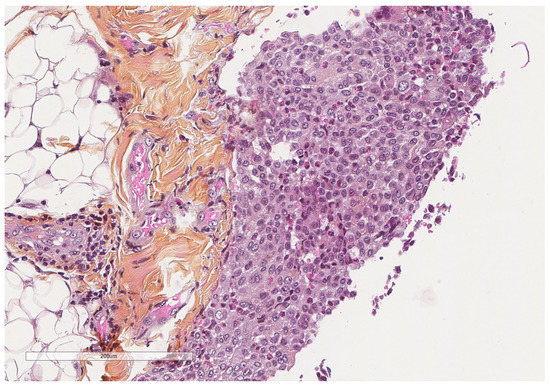

- Karpathiou, G.; Hathroubi, S.; Patoir, A.; Tiffet, O.; Casteillo, F.; Brun, C.; Forest, F.; Rahman, N.M.; Peoc’h, M.; Froudarakis, M.E. Non-specific pleuritis: Pathological patterns in benign pleuritis. Pathology 2019, 51, 405–411. [Google Scholar] [CrossRef] [PubMed]

- Karpathiou, G.; Anevlavis, S.; Tiffet, O.; Casteillo, F.; Mobarki, M.; Mismetti, V.; Ntolios, P.; Koulelidis, A.; Trouillon, T.; Zadel, N.; et al. Clinical long-term outcome of non-specific pleuritis (NSP) after surgical or medical thoracoscopy. J. Thorac. Dis. 2020, 12, 2096–2104. [Google Scholar] [CrossRef]